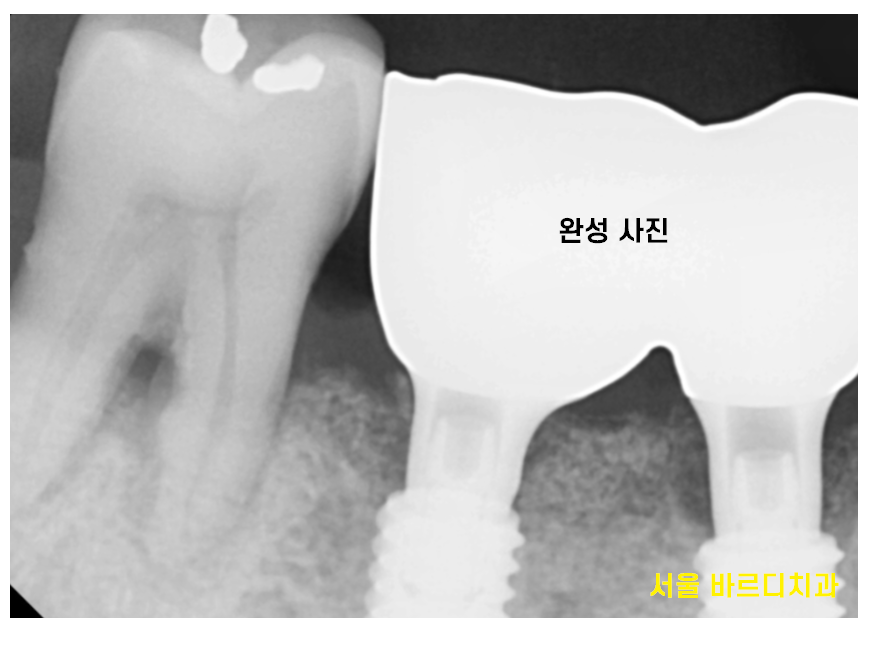

23.11.02

23.11.09

치료 후 잇몸 염증이 많이 사라지긴 했지만

한번 내려간 잇몸의 경우

회복이 어렵습니다.

정기적으로 하남시청치과에 방문하셔서

임플란트와 잇몸

두가지 모두 관리하시기로 약속하셨답니다~